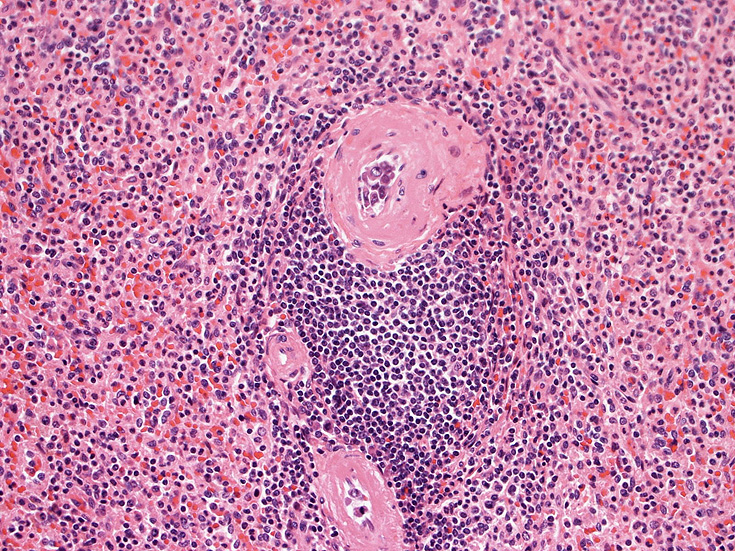

脾臓;白脾髄リンパ組織には腫瘍細胞は認めず、筆動脈内に増殖。

生検組織により血管内腔を塞ぐように大型異型リンパ球が増殖していることを確認することが診断の要件である。血管内増殖の病変分布が本病型では, 脳, 肺, 肝, 腎, 副腎, 皮膚, 骨髄など特有である。しかし大細胞型B細胞リンパ腫にはこのような臓器を選択的に侵襲するが, 血管内腔には増殖しないものがあることに留意が必要である。